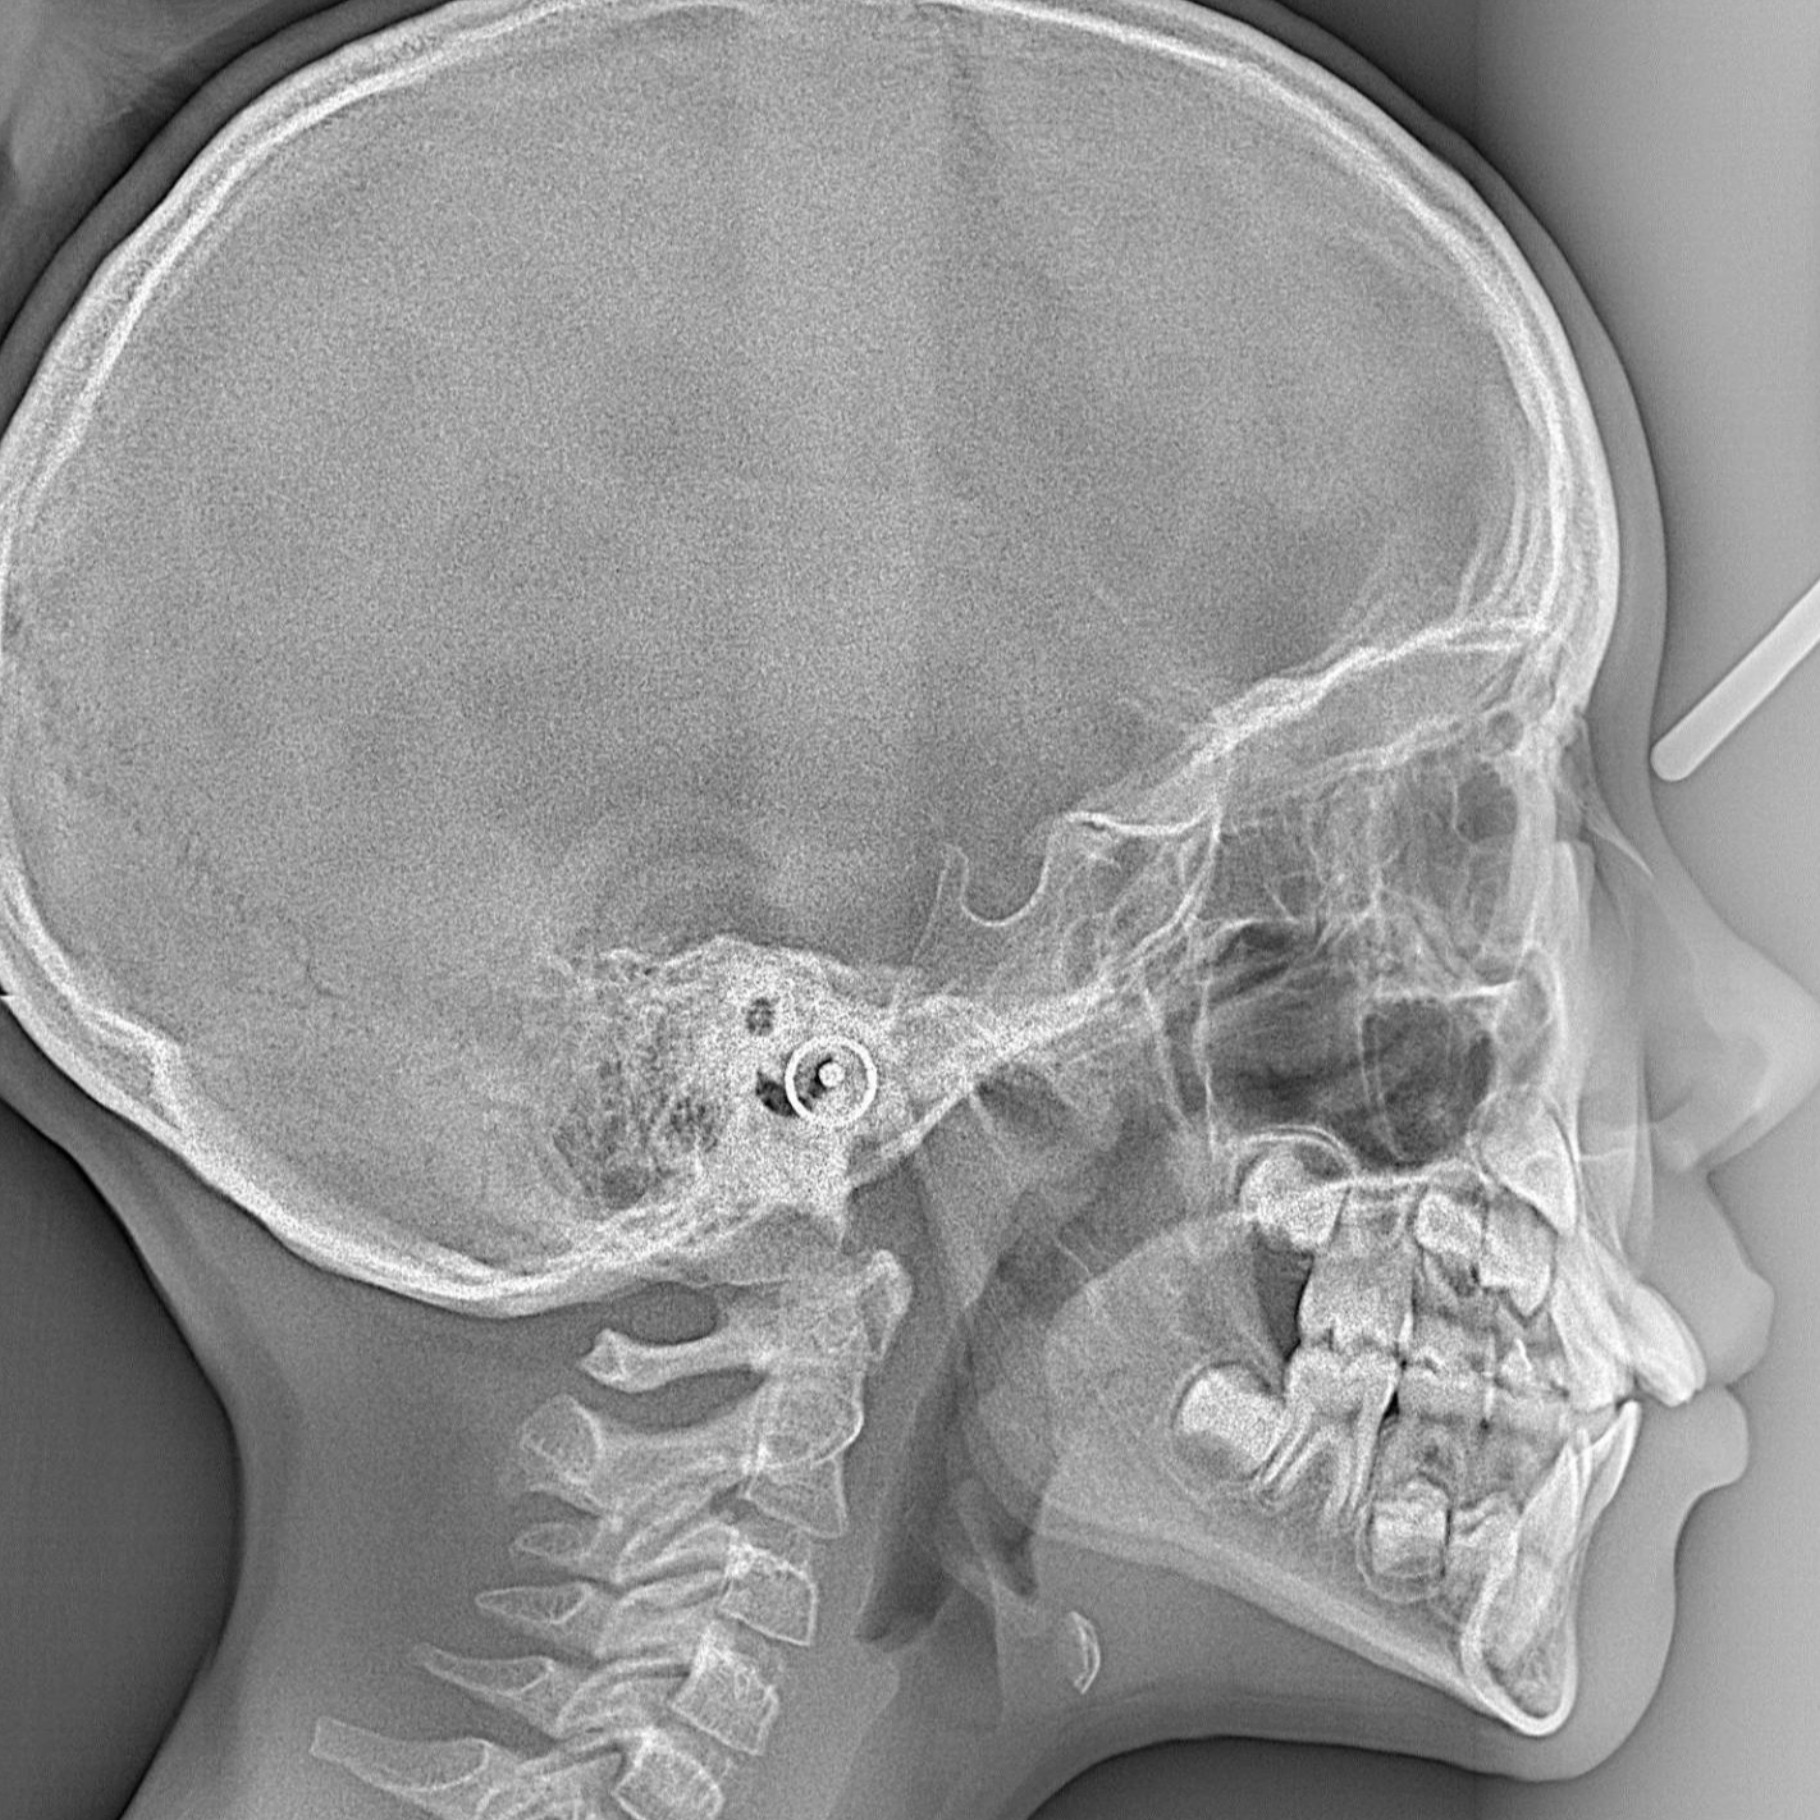

Lateral cephalogram in rohini lateral cephalogram test C-8/193 sec 8 rohini delhi 9811552279, 7827070020 A lateral cephalogram is a specialized X-ray of the side of the head used in orthodontics and oral surgery to analyze the growth and relationships of the dental, skeletal, and soft tissue structures of the skull. It provides detailed information to diagnose malocclusions, plan treatments like braces or orthognathic surgery, and monitor the progression and outcomes of orthodontic treatments. What it shows: Craniofacial Growth: It helps assess skeletal and dental structure changes, especially in children and adolescents. Dental and Jaw Relationships: It shows the relationship between the upper (maxilla) and lower (mandible) jaws and their positions relative to each other and the skull. Soft Tissue Profile: It can reveal information about the surrounding soft tissues, which is important for aesthetic evaluation. Tooth Inclinations: The inclination and position of teeth are evaluated, which helps in treatment planning, such as deciding on extractions. Why it's used: Treatment Planning: It's a standard tool for orthodontic and orthognathic surgery treatment planning, aiding in decisions like whether to extract teeth or perform surgery. Diagnosis: It helps in the diagnosis of skeletal and dental malocclusions. Monitoring Treatment: It's used to track changes and assess the progression of treatment over time. Research: Lateral cephalograms are also used in research to study craniofacial development and the effectiveness of different treatments.